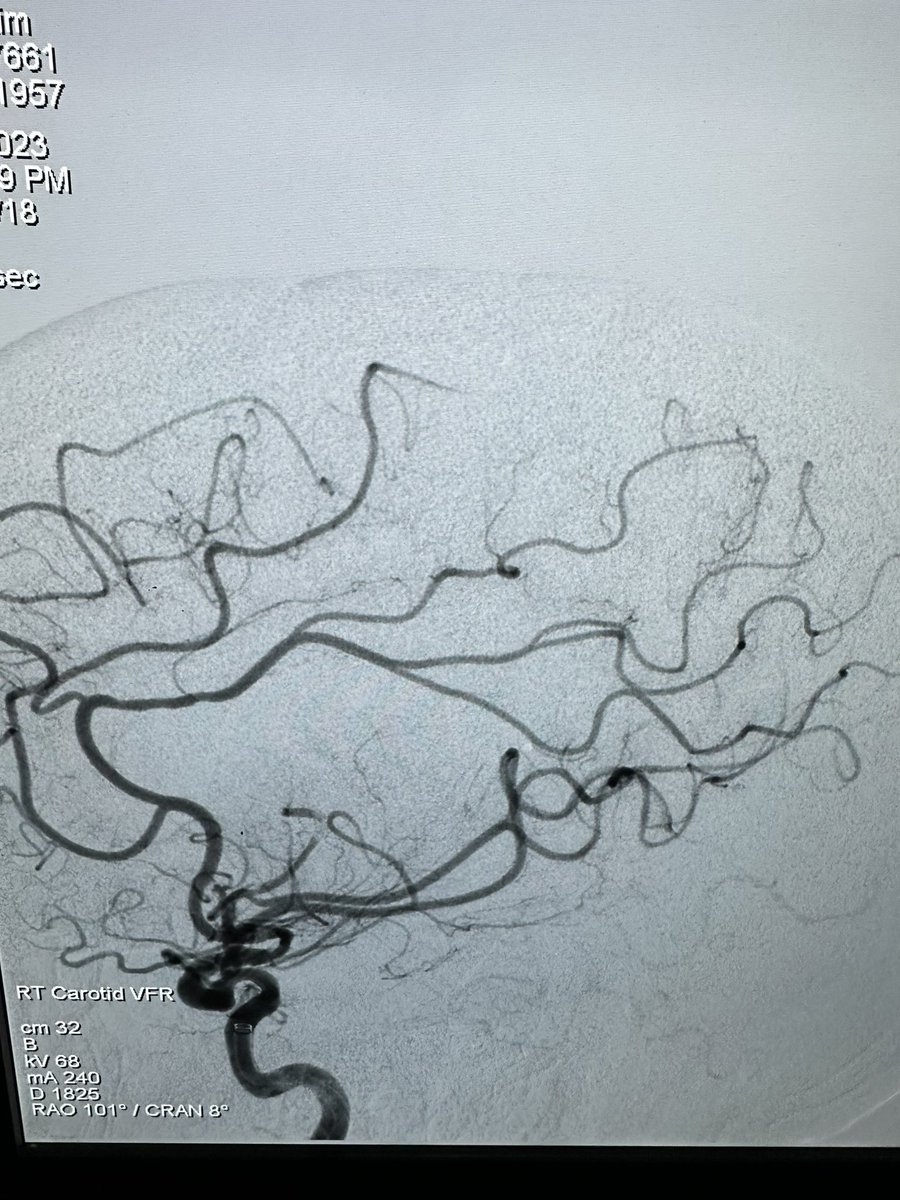

Great talk by @ShahidNimjee about VWF inhibiting aptamer for thrombolysis. This research has come along way and will improve stroke therapy in the future. It may be the beginning of the end of stroke mechanical thrombectomy. #SNIS2023 @OSUWexMed @NeurosurgeryOSU